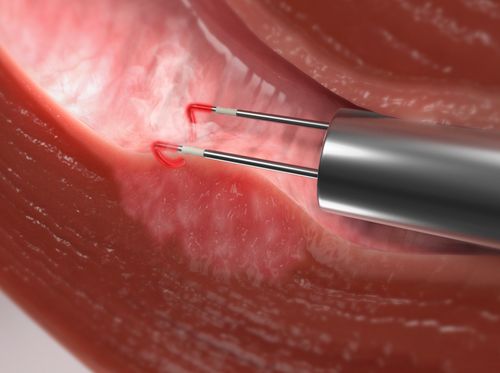

Sí. El tratamiento es quirúrgico y mínimamente invasivo:

- 🔬 Histeroscopía quirúrgica, para liberar las adherencias

✔️ Histeroscopía diagnóstica y quirúrgica